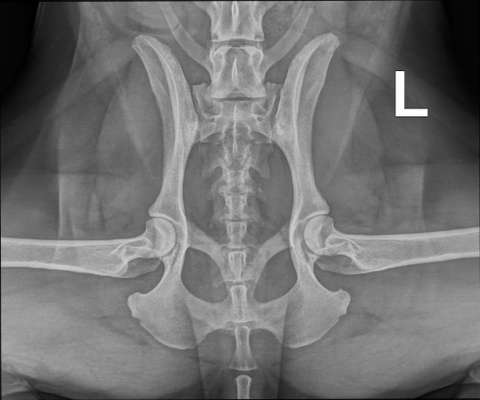

Hallo zusammen, aktuell beschäftigen wir uns mit dem Gangbild unserer Hündin und da ich hier im Forum immer mal interessante Videoanalysen gelesen habe, dachte ich, ich frag mal nach - vielleicht hat ja jemand Lust, sich die Videos mal anzusehen. Als wir Hina vor etwa einem Jahr aus dem Tierheim geholt haben, waren wir bei einer Tierärztin u.a. um mal auf das Gangbild zu gucken, weil ich fand, dass der Brustkorb beim Laufen immer stark hin und her wackelt bzw. sie mit dem Po stark wackelt. Zusätzlich sitzt sie oft, aber nicht immer im Welpensitz. Da das aber unser erster Hund ist, haben wir nicht so den Blick dafür, was "normal" ist oder nicht. Tierärztin meinte, alles in Ordnung (kein Röntgen). Vor ein paar Monaten hat uns unsere Trainerin auf das Gangbild angesprochen, woraufhin wir eine Zweitmeinung eingeholt haben. Zur Absicherung haben wir dort ein Hüft-Röntgen machen lassen, Ergebnis: "nicht so perfekt, wie es sein sollte, aber jetzt auch nicht so dramatisch, im Alter sicherlich Athrose". Falls sich jemand auskennt, ich hänge das Röntgenbild mal an. Physiotherapie zur Stärkung der Muskulatur und Nahrungsergänzungsmittel (Algenöl bzw. Kurkuma und Piperin von Vitalpfoten) wurden empfohlen. Wir haben keine genaue Diagnose gesagt bekommen, sollten für 10 Tage erst mal Schmerzmittel testen (1,5 Tabletten pro Tag Onsior 20mg / 22,5 kg Hund) und beobachten, ob wir Unterschiede im Verhalten feststellen, ob Hina Schmerzen hat/hatte. Termin zur Auswertung folgt noch. Daher sind die Videos entstanden und ehrlich gesagt, sehe ich keinen Unterschied. Auch sonst ist sie genau so aktiv wie vorher. Hinsichtlich des Passgangs bin ich auch immer wieder irritiert, wie viel davon "normal" ist, eben durch Tempoanpassung, und wie viel "zu viel". Da ich Hina aber auch täglich sehe und mir Sachen vielleicht weniger auffallen, würde mich interessieren, ob jemandem etwas auffällt, was ich bisher noch nicht gesehen habe. Ich freue mich auch über sonstige Hinweise zu dem Thema. Dankeschön!

Da also die RöBi im sedierten Zustand entstanden, kann man sich über die Hüfte eigentlich ein bisschen freuen (re. ist etwas schlechter als li., ja, ich hab Morgan-Linie und Norberg-Winkel hier nicht betrachtet, man möge es mir verzeihen …)

Kurz: es gibt wirklich furchtbare Hüftgelenke und diese hier gehören nicht dazu.

Der Bereich Sakrum / Kreuzbein und der Übergang zu den Vertebrae coccygeae / Rutenwirbeln kommt mir sehr ausgeprägt vor, hier könnte es ggf. Engstellen geben? Das mal vom Physio befunden lassen.

Außerdem wurde kein Bild von der Seite angefertigt. Meist röntgt man in zwei Ebenen (also in 2 Stellungen, das würde normalerweise einmal wie bei euch, bauchseits —> Richtung Rücken und dann zusätzlich von einer Seite zur anderen, während dein Hund auf der Seite liegt, gemacht = zweite Ebene). Es gibt ja auch die Möglichkeit, dass Spondylosen / Spondylarthrosen dieses Gangbild hervorrufen. Die könnte man dann in Seitlage erkennen.

Wie gesagt, kann man (ich) alles nicht abschließend beurteilen, ein Befund vom Physio bringt euch sicher wieder ein Stück weiter …